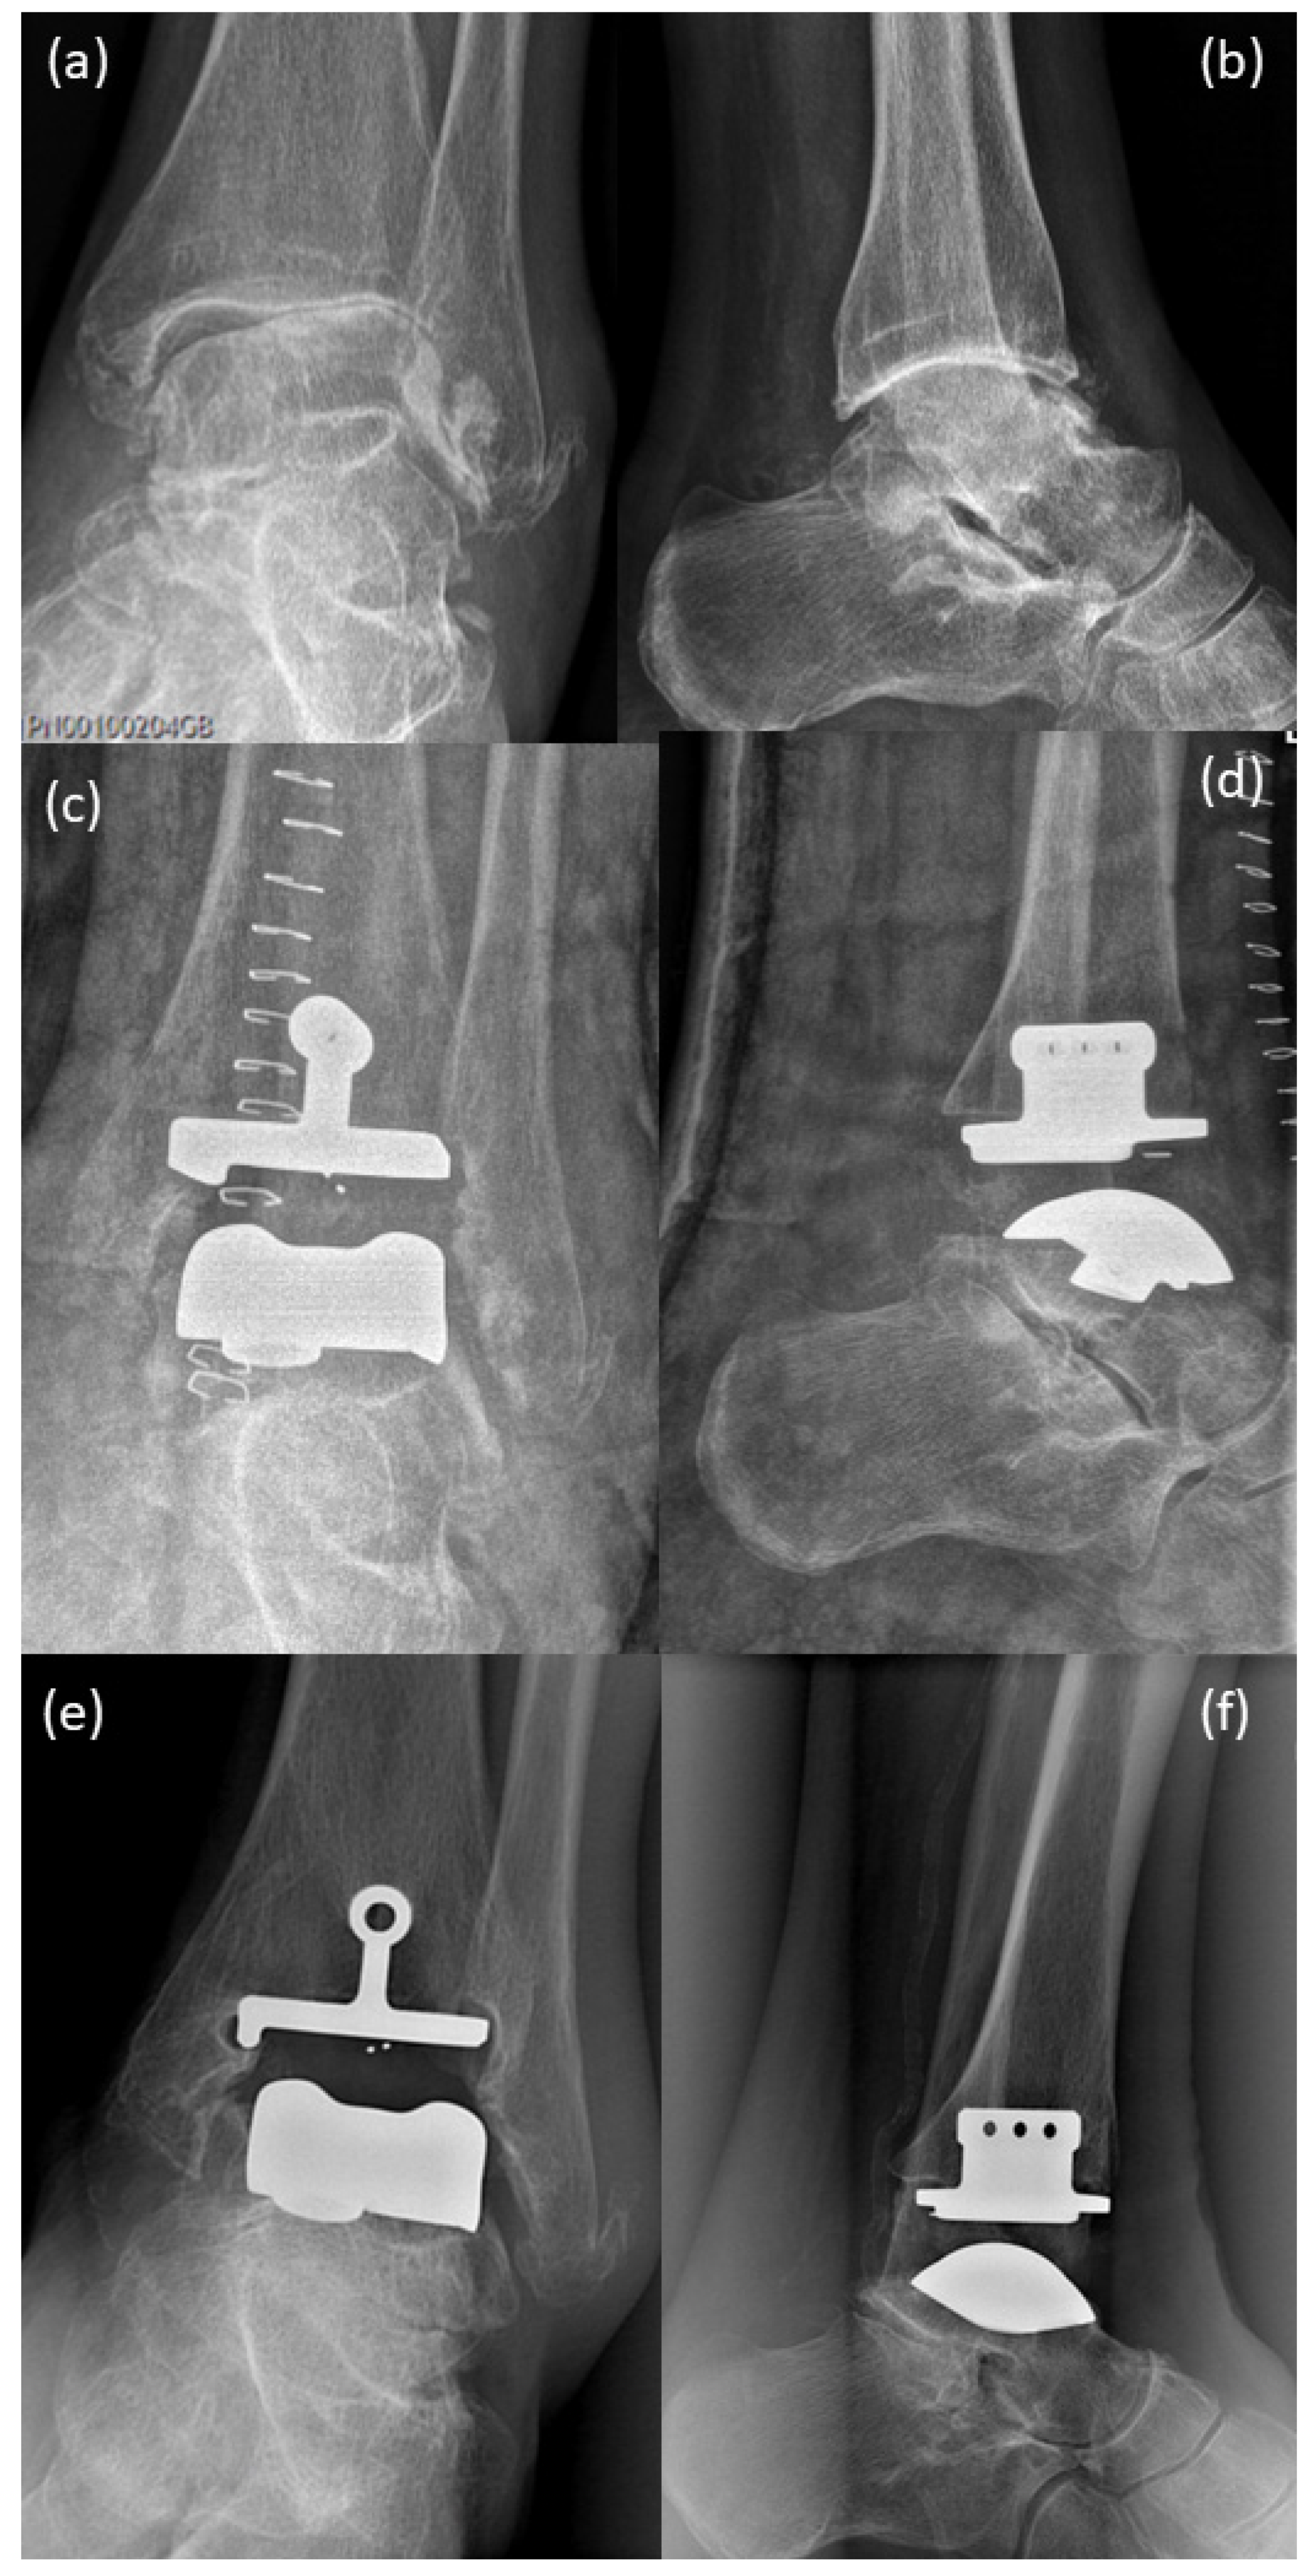

2. Case Presentation

3. Surgical Procedure

4. Postoperative Rehabilitation

5. Results